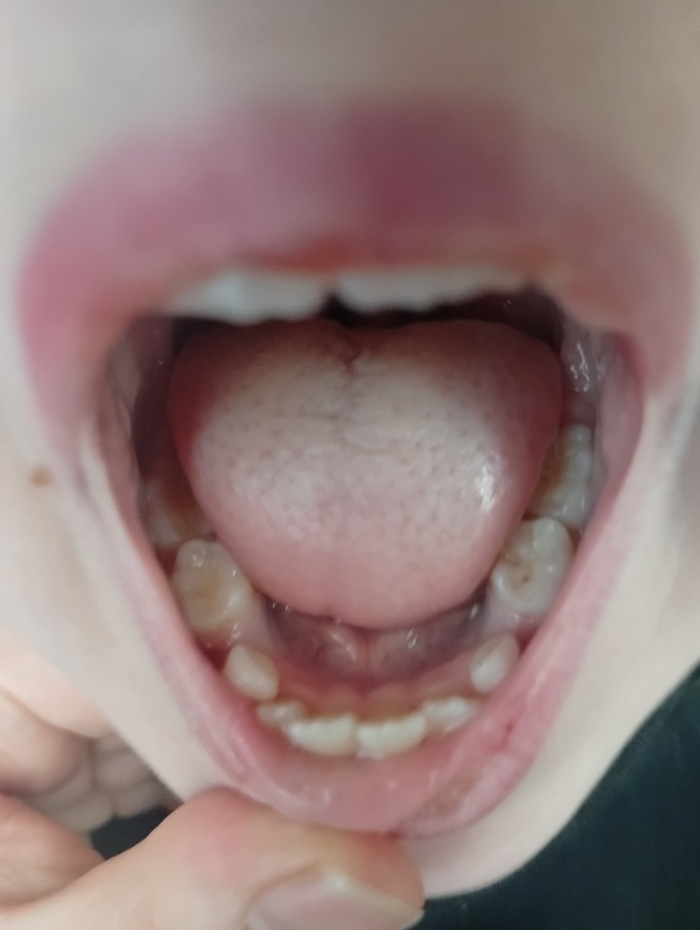

У моей дочери 7 лет начали появляться постоянные зубы и явно видно, что челюсть мала для таких больших зубов.

Прикреаиоа фото зубов и рентген от января. Внизу 2 зуба удаляли.